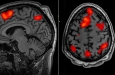

Слабость — это синдром, возникающий в результате возрастного снижения активности многих систем органов. Новое исследование, проведенное в Университете Ювяскюля (Финляндия), показывает, что более медленное время реакции и меньшая точность ответов при выполнении когнитивных задач связаны с более высоким уровнем слабости. Примечательно, что эта связь уже может быть обнаружена в позднем среднем возрасте, среди людей в возрасте от 57 до 70 лет.

"Наши результаты показали, что более медленное время реакции при выполнении когнитивных задач было связано с более высоким уровнем слабости в позднем среднем возрасте среди взрослых в возрасте от 57 до 70 лет", - говорит постдокторант Анна Тиркконен из Исследовательского центра геронтологии и факультета спорта и медицинских наук Университета Ювяскюля. «Что касается точности ответов, связь наблюдалась у всех участников, особенно среди женщин».

"Мы также обнаружили, что только точность реакции, но не время реакции, связана с развитием слабости", - добавляет Тиркконен. "Более того, связь зависела от того, какая конкретная область когнитивного функционирования изучалась".